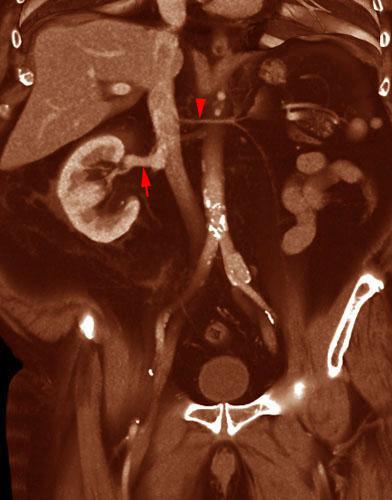

Hipoplasia renal 1